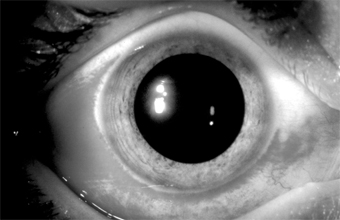

In adults, the conjunctiva of both tarsi-especially the lower tarsus-have papillae and follicles (Figure 5-3). Since pseudomembranes do not usually form in the adult, scarring does not usually occur. Superficial keratitis may be noted superiorly and, less often, a small superior micropannus (< 1-2 mm). Subepithelial opacities, usually marginal, often develop. Otitis media may occur as a result of infection of the auditory tube.

Figure 5-3

Figure 5-3: Acute follicular conjunctivitis caused by inclusion conjunctivitis in a 22-year-old man with urethritis. (Courtesy of K Tabbara.)